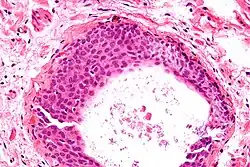

High magnification micrograph of a Brenner tumor showing the characteristic coffee bean nuclei which are also seen in Walthard cell rests. H&E stain.

- Cyst (may also be solid nest) of transitional type epithelium.

- Eosinophilic luminal secretions.

- Uniform nuclei with irregular borders and nuclear grooves (insert image).

They appear as white/yellow cysts or nodules that can reach a size of 2 millimeters. They typically have elliptical nuclei with a long groove (along the major axis) – so-called "coffee bean" nuclei.